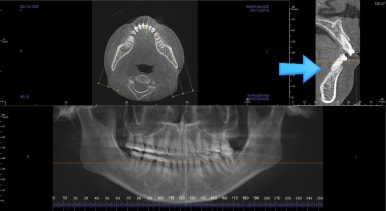

X-ray상에서의 아래 앞니 부분 쪽을 보겠습니다.

발치교정을 한 후에 무리하게 앞니를 뒤로 당겨 넣게 되면서 사진처럼 입안의 각도가 안으로 굽는 옥니가 되기 쉬운데요.

더 큰 문제는 잇몸뼈에서 벗어난 위치에 치아가 있었습니다.

겉으로 보면 잇몸에 덮혀 있으나 내부를 보면 뼈가 덮지 못하고 있기 때문에 매우 불안정하죠.

CT촬영으로 분석을 하니 턱관절의 방향이 다른 분들과는 구조적으로 달랐으며 운동범위가 제한이 될 수 밖에 없었어요. 이 부분을 충분히 설명 드린 후에 재교정을 시작했습니다.

부산연산동교정치과에서는 기도의 넓이, 부피, 코 안쪽 부분의 생김, 면적 등을 파악했습니다.

기다고 좁은 상태였다면 앞니를 뒤로 더 당겼을 때 기도가 좁아질 수 있기 때문에 교정 목표를 조절합니다.

다행히도 평균치를 보였기 때문에 안심하고 시작합니다.